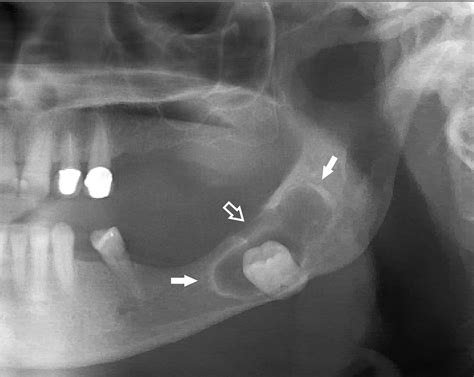

In most instances, a Maxillary Sinus Cyst is discovered incidentally. You might go to the dentist for a wisdom tooth extraction or to a doctor for a sinus infection, and the cyst appears on a panoramic X-ray or a CBCT (Cone Beam Computed Tomography) scan. Because these cysts are typically small and do not obstruct the main sinus drainage pathways, they rarely cause symptoms.

Panoramic X-ray General dental screening Dome-shaped radiopacity on the sinus floor.